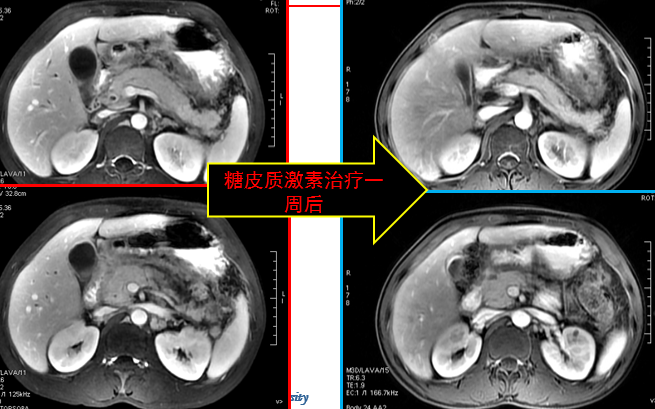

在影像学鉴别困难时,可结合类固醇激素实验性治疗,必要时结合血清学 IgG4 水平做出分析。

糖皮质激素治疗有效,能够使受累器官和组织恢复到原来的状态